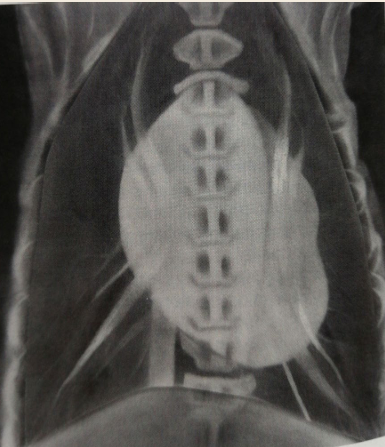

Total situs inversus

Heart is located towards the right side of thorax

Dextrocardia

Mirror image of the thoracic and abdominal organs

Situs inversus